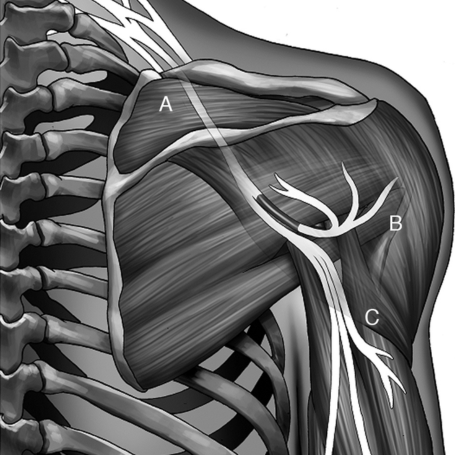

Lesiones nerviosas traumáticas

Tipos: Las lesiones nerviosas traumáticas pueden ser neuropraxia (daño leve), axonotmesis (daño del axón con preservación de la estructura) y neurotmesis (sección completa del nervio). Pueden afectar nervios periféricos o estructuras del sistema nervioso central.

Causas: Ocurren por traumatismos directos como accidentes, heridas por objetos cortantes, fracturas, compresión prolongada o estiramiento excesivo del nervio. También pueden deberse a cirugías o lesiones deportivas.